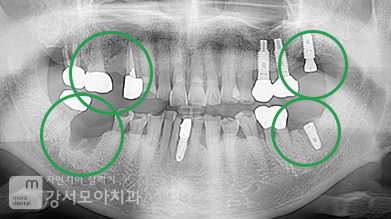

왼쪽 위아래 어금니쪽 염증이 아주 심했던 사례로

치아가 심하게 흔들리고

윗치아는 상악동, 아랫 치아는 하치조신경이라는 신경관까지

염증이 존재하였던 고난도 임플란트 케이스입니다.

뼈가 많이 녹아있었고 뿌리 부분 윗쪽으로

cyst(낭)라는 구조체 존재하였던 고난도 임플란트 케이스입니다.

오른쪽은 맨 끝 치아,

왼쪽은 큰어금니 2개가 흔들림이 심하여 발치하였으며,

심한 염증을 가라앉히고 뼈의 양이 적어

임플란트 주변 뼈를 형성하였습니다.

전신질환이 있으셔서 이 부분을 고려하여 식립하였습니다.